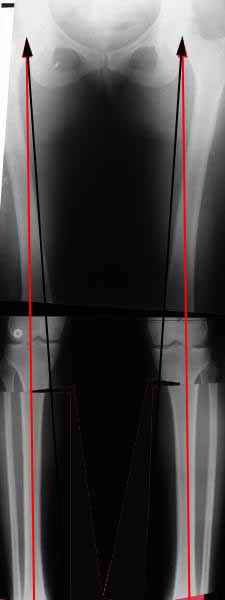

. On the right leg you can see some of the tools (from the tool bar above) applied to demonstrate a mild mech-axis varus of about 5 degrees.

On the left the bone landmarks used in the anlaysis are shown.

The data for the analysis are in the XLs sheet below, exported from the program automatically.

I have given a label of the abreviations and some normative values.

In essence she has a mild mech-axis varus of 7 degrees with some contribution from the femur (2) degrees and more from the tibia (6 degrees), none from the joint.

The analysis took about 6 mins.